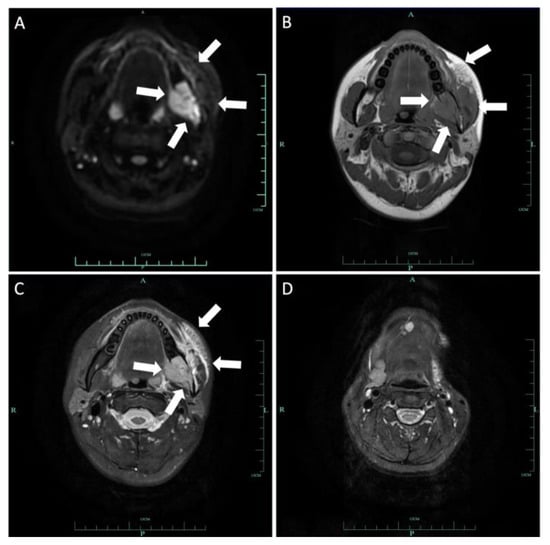

2.1. Case 1